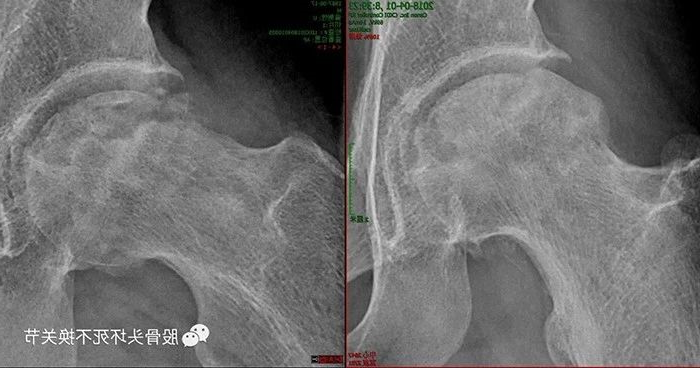

患者住院期间专家对双侧股骨头采用体外冲击波治疗,出院后每月治疗1次。

这是患者出院半年以后的状况,右侧股骨头可见囊变区骨密度提高,关节间隙保持完好。

左侧股骨头密度明显升高、均匀,基本达到了正常骨密度要求。病人原本准备出院半年后进行关节置换,体外冲击波治疗却给他带来了意想不到的效果。